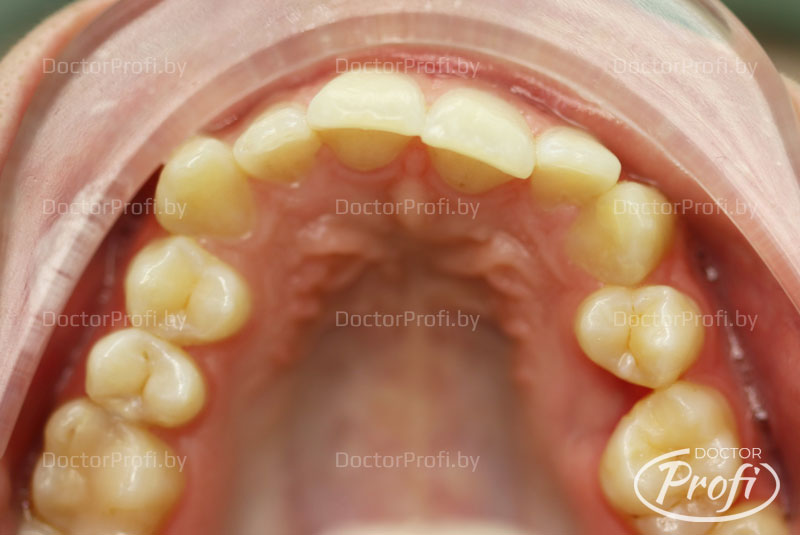

Пациентка обратилась в клинику с жалобами на неэстетичный зубной ряд. Возраст - 21 год. На консультации у ортодонта были выявлены следующие проблемы с прикусом: дистальный прикус, глубокое травмирующее резцовое перекрытие, сужение и укорочение зубных рядов, повороты зубов, скученность, отсутствие зуба 15.

До